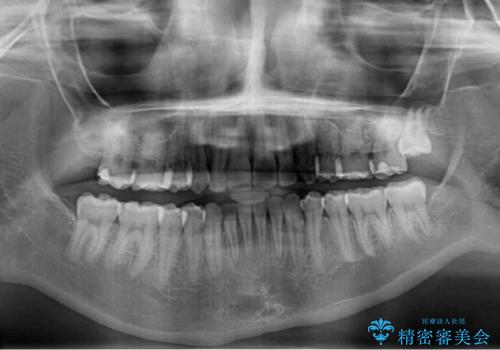

片側の八重歯であり上顎の正中がずれていたため、上顎左右第一小臼歯2本を抜歯して排列することとしました。

下顎の骨格的なズレが大きかったため、上下歯列のバランスが取れるか心配でしたが、上下ともに左右対称に近い歯列で治療を終えることができました。